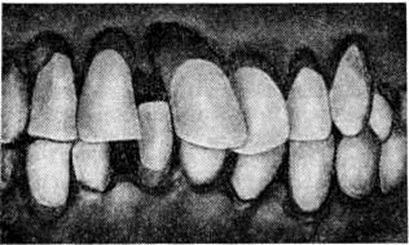

Развившаяся стадия Пародонтоз, как правило, характеризуется наличием генерализованного гингивита, пастозностью дёсен с явлениями застойной гиперемии, их кровоточивостью, наличием пародонтальных карманов глубиной 5—6 миллиметров и более, в большинстве случаев с выделением из них гноя. Отмечается обильное отложение плотного поддесневого камня, который в отличие от наддесневого проникает в глубь пародонтальных карманов в виде тонких зернистых наслоений, плотно прикрепляющихся к корням зубов. Зубы становятся подвижными, часто смещаются, поворачиваются по оси (рисунок 3), выпадают. Между зубами, ранее плотно соприкасавшимися, образуются свободные промежутки (смотри полный свод знаний: Диастема, Трема). Подвижные зубы травмируют окружающие ткани и усиливают воспаление. При обнажении шеек и корней зубов открытые их зоны подвергаются длительному раздражению при приёме пищи, вдыхании охлаждённого воздуха, разговоре и становятся источником болей. Отмечаются смещение зубов, нарушение дикции, у некоторых больных появляется неприятный запах изо рта. Общее состояние, как правило, страдает незначительно, иногда отмечается субфебрильная температура. Но в ряде случаев состояние больных резко ухудшается.